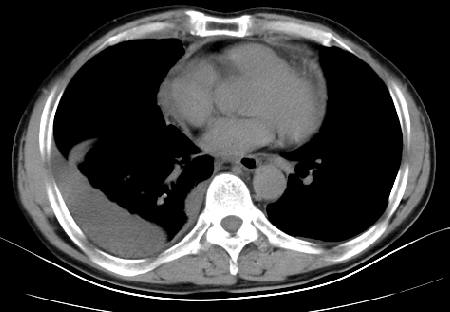

以下是引用草之原在2009-5-2 19:29:00的发言:[br]1.考虑右侧中心型肺ca纵膈淋巴结转移,双侧胸腔积液及右侧叶间裂积液,心包积液。[br]2.两肺上叶病灶,纵膈窗显示部分病灶硬化,考虑:结核。[br][br] [br]

以下是引用ct诊断高手在2009-5-2 19:08:00的发言:[br]我考虑右侧中央型肺癌 伴右肺节段性不张,两肺及纵隔淋巴结转移,右侧胸腔积液。

以下是引用zjzjr在2009-5-2 20:16:00的发言:[br]肺结核,转移瘤.纵隔淋巴结转移或淋巴瘤,右侧包裹性积液、斜裂积液。心包积液。